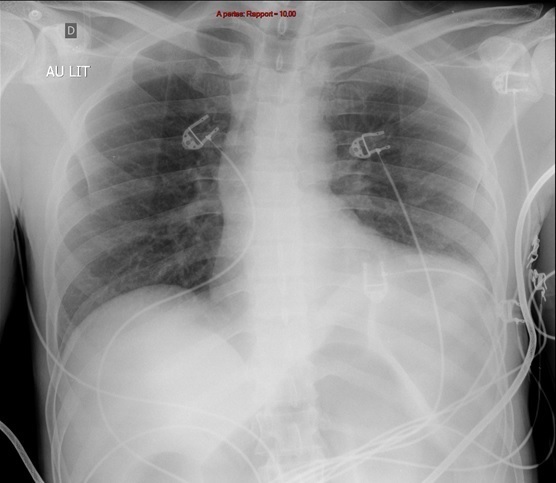

Une radiographie de thorax est réalisée.

Question 8 : Parmi les propositions suivantes, laquelle (lesquelles) est (sont) exacte(s) ?

La radiographie est de qualité médiocre (cliché au lit), mais ne retrouve pas d’anomalie parenchymateuse ni médiastinale évidente. Il existe en revanche une dilatation des anses digestives, avec des haustrations coliques visibles, probablement responsables d’une surélévation de la coupole gauche.